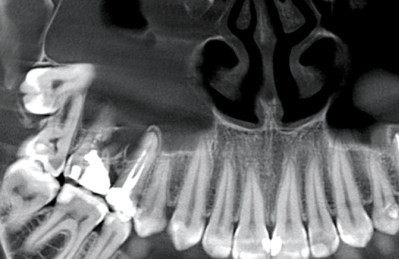

• панорамное костно-челюстное рентгенологическое сканированиепровести конусно-лучевую томограмму;

• сделать панорамное костно-челюстное рентгенологическое сканирование;

• выполнить точечный рентгенологический снимок зуба и прочее.